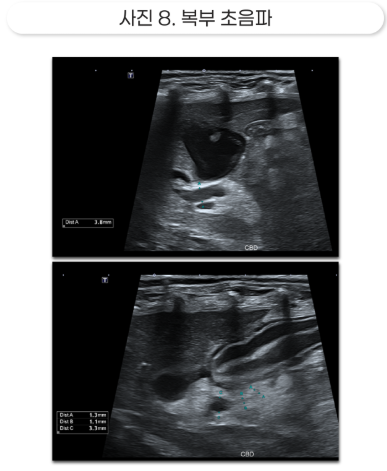

특히나 환자 정도로 심한 췌장염 환자는 EHBO (Extra Hepatic Biliary Obstruction) 가 발생할 수 있습니다.

EHBO는 담즙을 분비하는 담관이 간 외의 원인으로 인해 폐쇄되는 상태로, 구조상 개는 담즙이 십이지장 내로 분비되는 구멍과 췌장이 십이지장으로 소화액을 분비하는 구멍이 동일합니다.

췌장염이 심하게 발생하는 경우 췌장의 부종이 이 구멍을 압박하게 되어 담즙도 제대로 분비되지 않는 경우가 종종 발생하게 됩니다.

담즙의 배출이 막히게 되면 황달이 발생해 간세포에 독성을 유발하고, 고여있는 담즙은 세균 증식이 쉽게 일어나 세균성 담도염을 유발할 수 있습니다. 이를 모니터링하기 위해 환자는 입원 중 매일 혈중 빌리루빈 수치를 측정해 적절한 시기에 대응할 수 있도록 관리했습니다.

또한, 빌리루빈 수치가 정상 이상으로 오르고 초음파상 췌장 실질이 염증으로 인한 괴사와 화농성 복수, 담즙의 배출이 원활하지 않아 발생하는 담관의 확장이 관찰되는 등 EHBO 발생 소견이 확인되었습니다.

황달로 인한 간의 손상을 해결하기 위해 선택한 것은 담낭 천자였습니다.

담낭 천자는 현재로썬 황달의 원인을 해결하는 것이 아닌, 저류된 담즙을 제거해 일시적인 황달의 개선을 유도하고, 간의 손상과 담관염의 발생을 지연시키는 일시적인 조치이며 담낭 파열의 가능성이 있는 위험한 시술이나 빠르게 상승하는 간 수치를 지켜볼 수만은 없었습니다.

다행히 담낭 천자는 성공적이었고, 저류된 담즙을 모두 제거할 수 있었습니다.

담낭 천자 이후 일시적인 빌리루빈 수치의 하락이 확인되었으며, 일시적인 재상승이 확인되었지만 이후 빠른 속도로 황달의 개선이 관찰되었습니다.